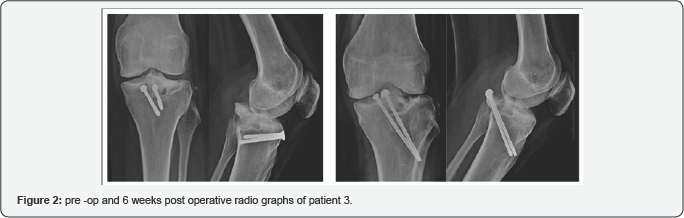

All the patients underwent surgery in regional anesthesia (spinal). The patient was put in prone position and apneumatic tourniquet was applied to the thigh to minimize bleeding into the operating field. The fracture was approached using an "L" shaped incision (Burke and Schaeffer approach) [17] with the vertical arm medially and distally and the horizontal arm of the incision marked parallel and slightly proximal to the joint line, marked using the fluoroscopy. The interval between the medial border of medial gastronomies and semi membrane osus muscle was developed. After dissecting the medial border of the medial gastrocnemius, the muscle was retracted laterally to expose the posterior joint capsule. The fracture fragment and bed was universally found to be sclerosed and was freshened using an electrical burr until cancellous bone was evident. The PCL tendon was freed from the fibrous tissue and through an ethibond suture was pulled distally to restore length and tension in the ligament. The fracture was then reduced; reduction checked under C-arm and was fixed using partially threaded cannulated cancellous screws (4mm dia.) with washer as distal as possible in PCL fossa. One of the cases (case 3) had a very large fragment and required 2 screws for adequate fixation. The wound was closed after deflating tourniquet and obtaining hemostasis.

The mean follow-up period was 8(range, 4-12) months. All patients achieved union at mean 12(range, 10-14) weeks. VAS scores reduced from mean 6(range, 5-7) to mean 1(range, 0-2) at 6 weeks postoperatively. None of the patients required regular analgesia in the post operative period beyond the first week. The range of movement (ROM) improved from mean 96.60 to 113.30. Full extension was achieved in all patients while 1 patient had restriction of terminal flexion at 3 months post operatively. All which improved to no laxity in 3 cases and grade I laxity in 1 4 patients had grade III posterior drawer test pre-operatively case. There were no wound complications (Figure 1‐3).

Lysholm scores preoperatively ranged from 69 to 79 (mean 74.5). This improved to a mean postoperative Lysholm score of 91(range 88‐94). All the patients were back to their pre‐injury level of activities after 6 months of surgery except one patient who is still to complete her 6 month follow-up Table 1.